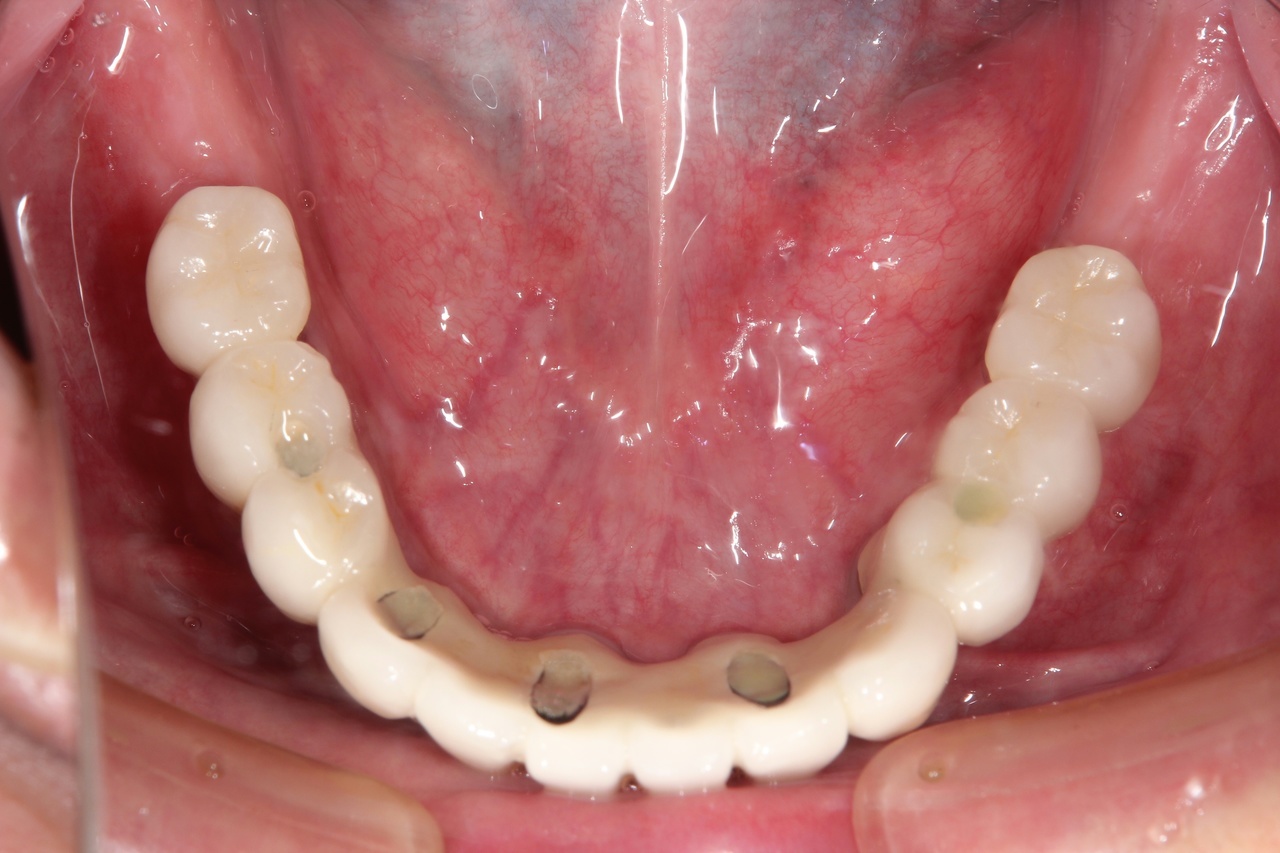

最終的な被せ物装着

インプラントがしっかり骨に定着したら、型取りをして、最終的な被せ物を製作し、装着します。

完成後のレントゲン写真

最終的な被せ物を装着した状態のレントゲン写真。

(今回は下顎ですが、その前に上顎は治療済みです。)